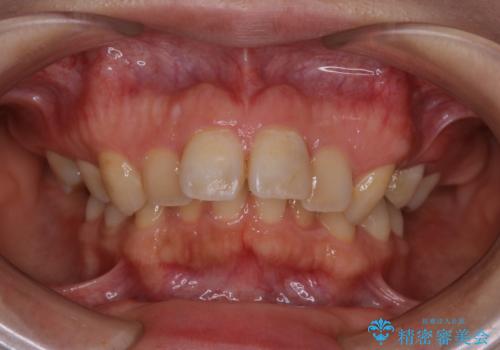

- インビザライン矯正治療の開始前にキレイな状態にしたいとのことでした。PMTC30分コースを行ってからインビザラインの型どりを行いました。

インビザラインの型どり・スキャニング(光学3Dスキャナー「iTero Element」)の前に、プラークや歯石・ステインを除去することで、ご自身本来の歯の状態となるため、綺麗なスキャニングが行えます。より精度のよいマウスピースを作成するために、PMTCを行うことをおすすめしています。